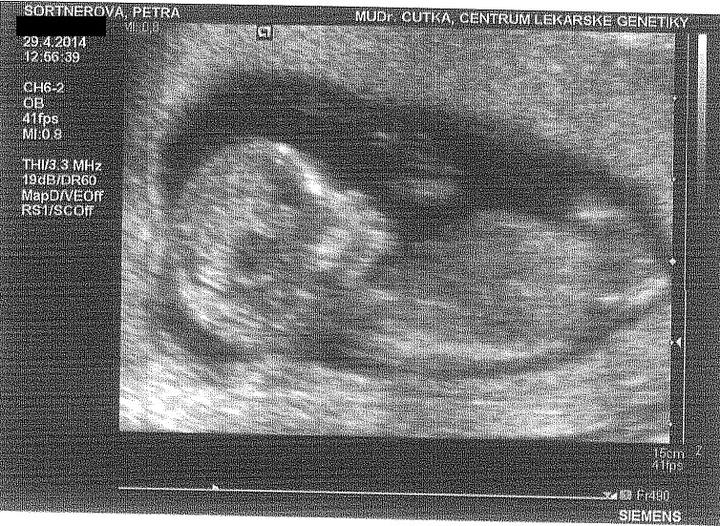

Tak včera jsem byla v nemocnici se špiněním... Nepřišlo se na důvod, dostala jsem prášky a uvidí se co dál. Ella je v pořádku, váží 944g, lpacenta se neodlučuje i čípek je ok. Ale to, co mě děsí, je, že mám pořád placentu přes DDS. Říkali mi to už ve 20tt, ale prý se ještě může vytáhnout. Ale když je tam i teď ve 28tt, tak nevím, jestli se ještě může vytáhnout. Jak jste na tom vy,co to máte stejně?

Dnešní poradna dopadla moc dobře. Ella odpovídá přesně 24+4, má dostatek plodové vody, je aktivní, srdíčko zase krásně tlouklo. Zatím je hlavičkou nahoru, ale je prý ještě čas.

Tak dnešní screening dopadl na 1*... Všechno naprosto dokonalé, miminko zdravé, testy i UZ v pořádku. Mimčo měří 6 cm. Bylo krásně natočené a mávalo nám ručičkama. Paní doktorka nám vše krásně vysvětlila a ukázala... Manžel byl nadšený a je pyšný, protože budeme mít na 80% holčičku 🙂 Jsme nesmírně šťastní 🙂